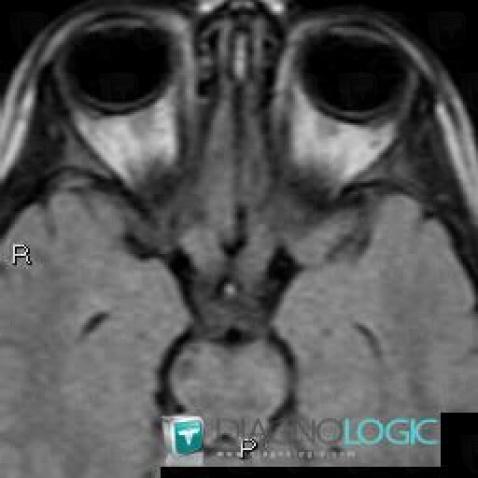

Gliome-nerf optique , OEil, IRM

Voici les informations spécifiques à l'image clé ci dessus:

- Diagnostic Gliome du nerf optique , Localisation(s) Oeil, comportant les gammes Lésion du nerf optique